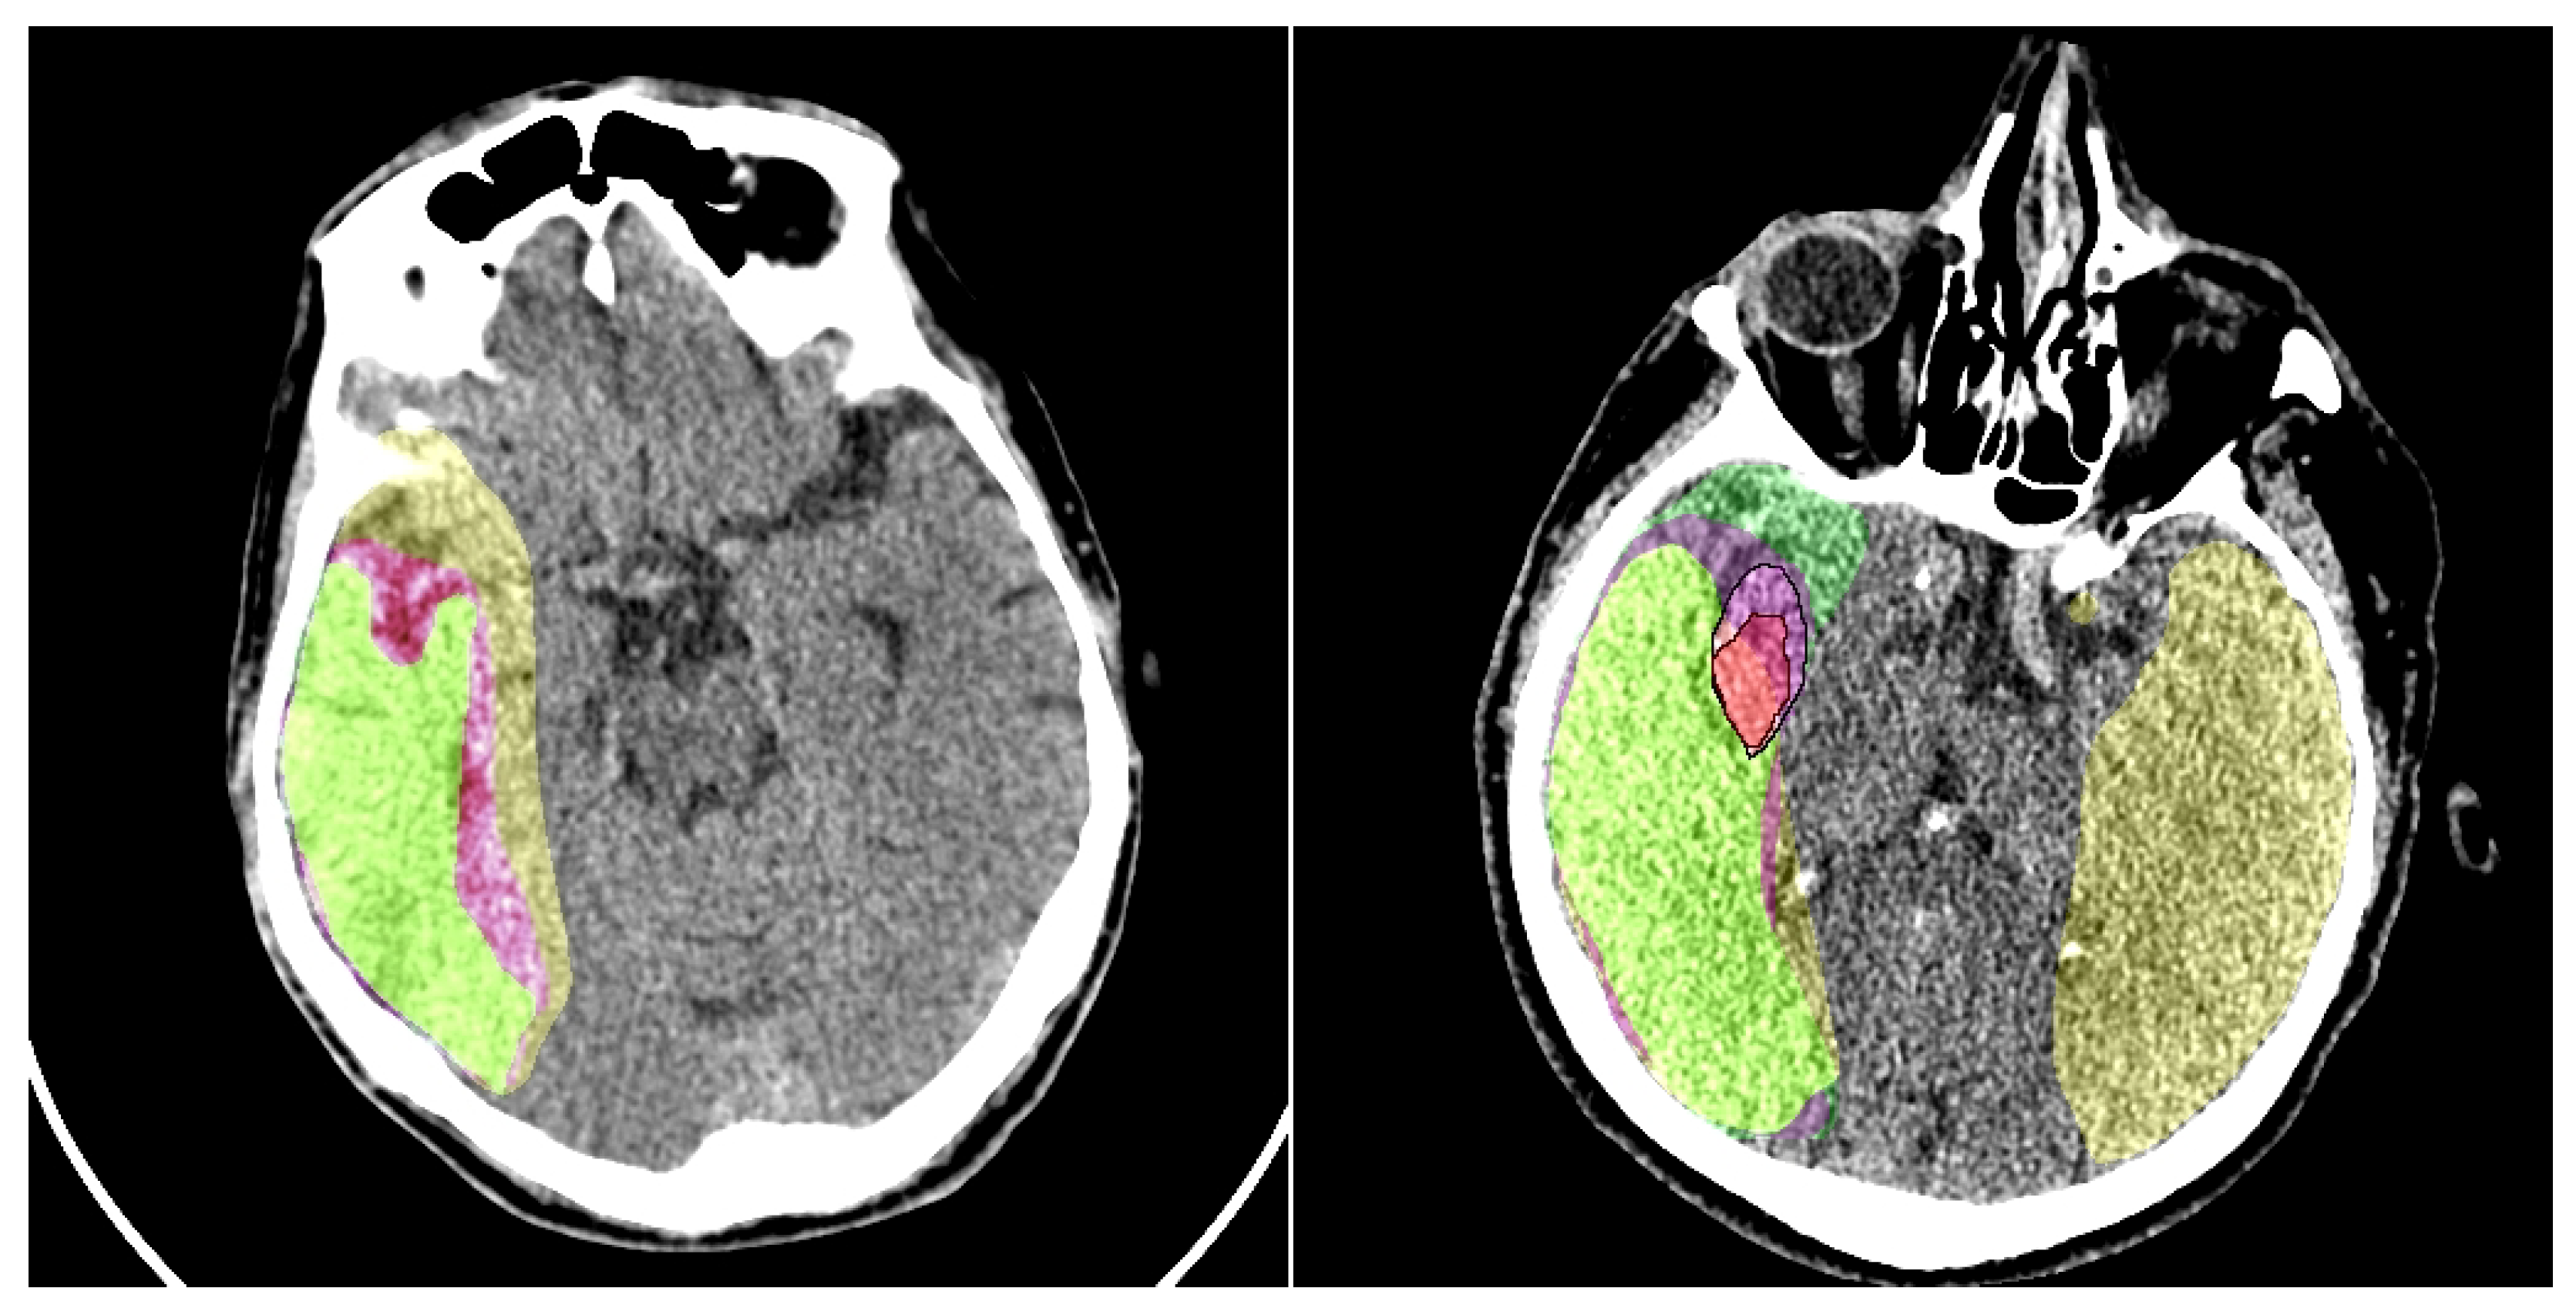

To substantiate our claims regarding improved lesion delineation, particularly for subtle penumbra regions where small intensity variations can critically affect boundary label assignment, we conducted an expanded quantitative and qualitative analysis incorporating boundary-sensitive metrics and failure case visualization. On the CPAISD test set, our CP-SwinUNet configuration achieved a mean HD95 of 8.2 mm ± 1.7 (vs. 11.4 mm ± 2.3 for baseline SwinUNet without preprocessing) and an ASSD of 1.83 mm ± 0.41 (vs. 2.67 mm ± 0.59), demonstrating significantly tighter boundary alignment with ground truth contours. Additionally, we computed the trimap F-measure (using a 5-pixel boundary band around manual annotations) and observed a 6.9% relative improvement (0.742 → 0.793), confirming enhanced precision-recall balance specifically at lesion rims. Qualitative failure analysis revealed that in 12 of 809 test slices (primarily cases with minimal gray-white matter contrast or early cytotoxic edema) both baseline and CP models exhibited boundary instability, occasionally mislabeling 1–2 pixel-wide transition zones. However, in 9 of these 12 cases, our preprocessing module successfully stabilized segmentation by adaptively enhancing local contrast and suppressing noise-induced oscillations, as visualized in Figure 7. These slices represent the most diagnostically ambiguous scenarios, where even expert radiologists exhibit inter-rater variability. The consistent reduction in HD95 and ASSD, coupled with improved trimap F-measure and visual boundary coherence, provides strong empirical support for our claim that the proposed preprocessing enhances structural delineation fidelity, especially in clinically critical, low-contrast penumbral zones.

The visual results of our preprocessing module are presented in Figure 7. We conduct a comparison of the baseline segmentation model’s performance with and without the addition of our model. It should be noted that the output of the preprocessing module does not always enhance the perceptual quality of the image for humans; however, the preprocessing highlights certain features in the image that subsequently assist the segmentation network in improving its predictions.